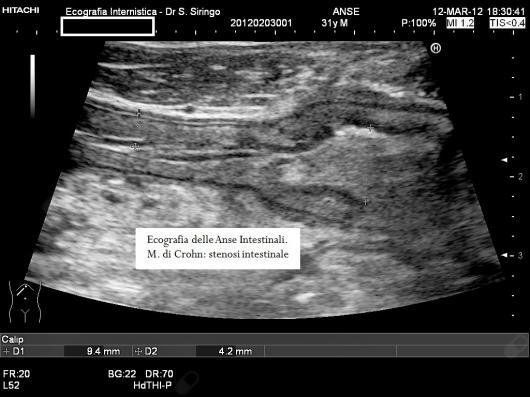

E’ una metodica di primo livello da impiegare nello studio dei disturbi addominali. In particolare, insieme ad alcuni specifici esami di laboratorio, permette un’agevole diagnosi differenziale tra colon irritabile e malattie infiammatorie dell’intestino quali la m. di Crohn e la colite ulcerosa. Inoltre, nel sospetto di m. di Crohn, consente di orientare rapidamente la diagnosi permettendo di rilevare l’ispessimento delle pareti del piccolo intestino e del colon che contraddistingue questa malattia.

Nella m. di Crohn, dopo la diagnosi, è un utilissimo mezzo per seguirne l’evoluzione, la risposta alla terapia e rilevare le possibili complicazioni quali ascessi o restringimenti dell’intestino.